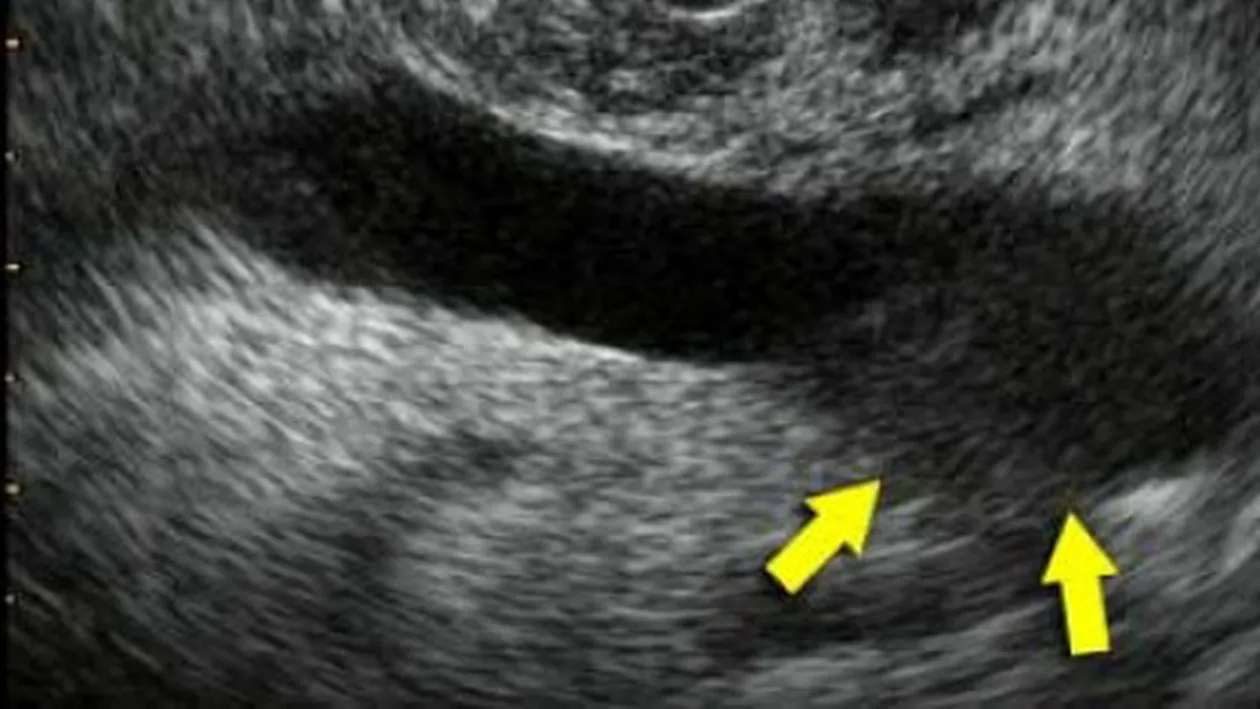

Jake “The Snake” Roberts va trebui sa suporte o interventie chirurgicala prin care sa-i fie scoasa tumoarea canceroasa pe care o are la genunchi. Anuntul a fost facut chiar de el, acesta confirmand faptul ca tumoarea se afla undeva in spatele genunchiului.

Cei de la TMZ scriu ca acesta urmeaza sa fie operat de urgenta. Umflatura pe care o are este destul de mare, iar dupa ce a observat ca aceasta creste, a mers la un consult medical. Doctorii i-au dat cea mai proasta veste: cancer.